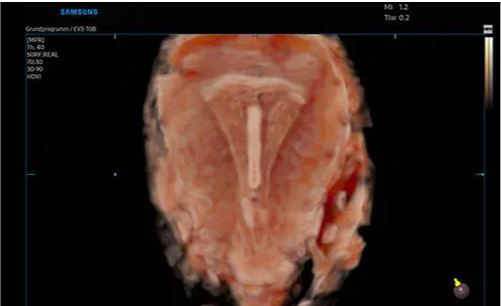

Modes d’imagerie: noir et blanc, doppler couleur, 3D/4D

– CrystalLive™ est le moteur d’imagerie échographique Samsung le plus récent, avec un traitement d’image 2D, un rendu 3D et un traitement du signal couleur améliorés, dans lequel on obtient des performances d’image enrichies et un flux de travail efficace pendant les cas complexes.

Images 2D sophistiquées traitées par CrystalLive™: CrystalLive™ vous aide à poser des diagnostics plus sûrs grâce à des images 2D fondamentales. Parmi les principaux avantages des images 2D, citons les images supprimées des ombres, les artefacts de halo atténués et les zones floues atténuées.